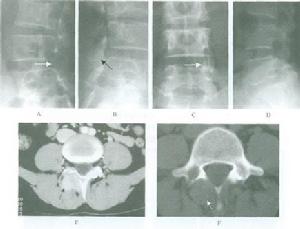

普通X線檢查中,頸椎側位片和矢狀面的斷層對Ⅰ型骨折的診斷非常有用。側位片可顯示骨折線通過樞椎椎體背側,椎體的前方大部分和寰椎一道向前移位,並伴屈曲或伸展的成角畸形,而其椎體後、下部位仍在原處,位於C3椎體上方的正常位置,斷層以片可清楚顯示骨折線及骨折塊移位的情況。開口位片和冠狀面的斷層片對Ⅱ型骨折的診斷非常有價值,可顯示樞椎側塊塌陷、寰椎側塊進入樞椎上關節面。

CT尤其是CT三維重建對了解骨折的全面信息非常重要。

另外對於一些移位很小的樞椎椎體矢狀骨折和後緣冠狀骨折僅攝正側位X線片容易漏診,故對可疑患者應加攝張口正位和屈伸側位X線片。有學者指出,觀察樞椎椎體骨折最清晰的手段是CT薄層重建。對本病的鑑別診斷極有幫助。